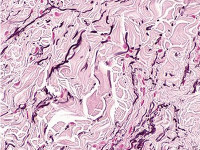

PA:Histologisch ziet men een toename van elastine, en/of abnormaal gevormde (dikke) elastinevezels. Het histologisch beeld lijkt op dat van een naevus elasticus.